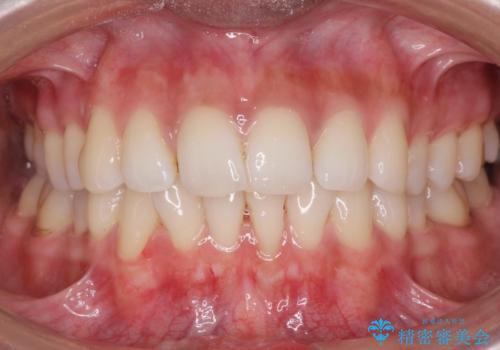

着色が気になる(エアフロー)

- 着色が気になるとの事で来院。

エアフローでしっかり着色を取り除きました。

着色が目立たなくなり大変満足して頂けました。